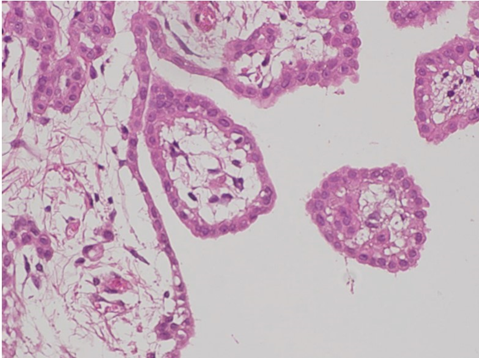

Microscopic examination showed that a papillary pattern accompanied by a glandular pattern, and the papillary areas were lined by a single cuboidal mesothelial cells (Figure 3), with one case (Figure 4, Case 8), having a mild nuclear atypia. In general, the mesothelial cells lacked mitotic activity. In addition, less than 1% of cells were positive for MIB-1 antibody (Figure 5). Immunohistologic studies showed a positive calretinine, CK7 (Figure 6) and D2-40 (Figure 7) and a negative CEA. In case 8, submesothelial invasive tumor of higher cytologic grade was detected in one of 23 sections from resected specimen.

Figure 3: Hematoxilin-eosin staining of case 4 (left) and case 1 (right).

Figure 4: Mild nuclear atypia was found in Case 8.